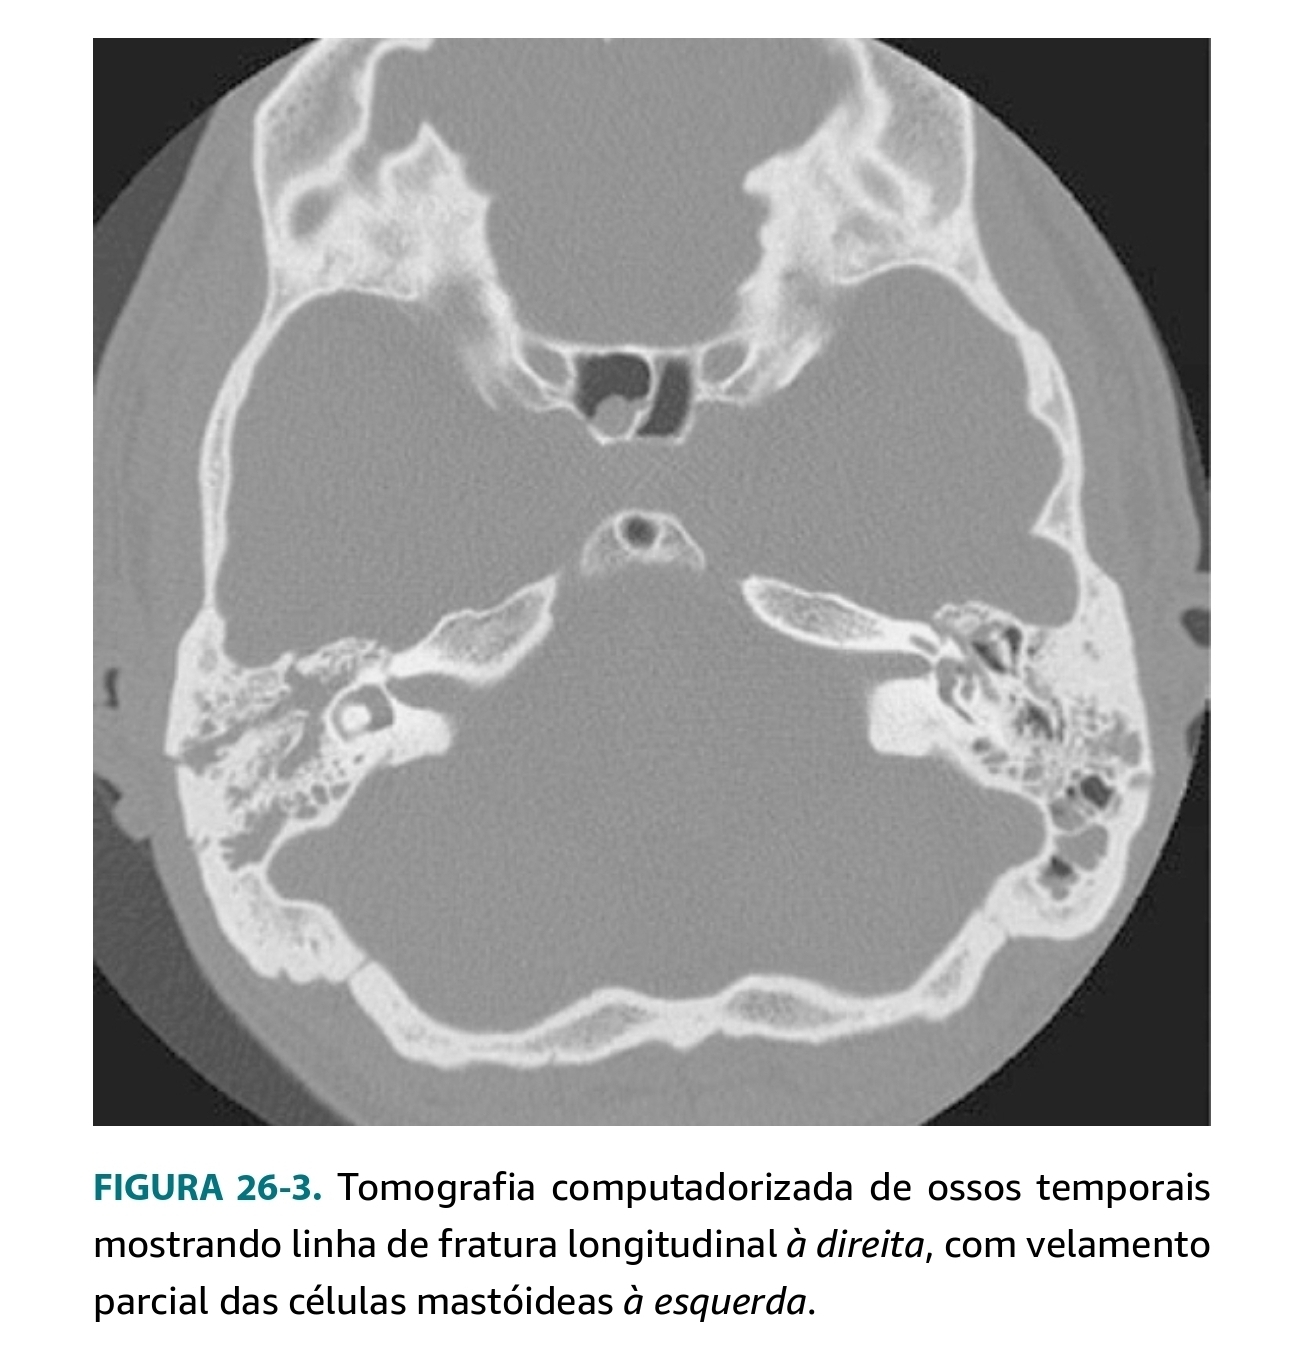

Cite o checklist de estruturas que devem ser avaliadas em uma tomografia de um trauma de osso temporal, como as abaixo.

A

• Localização e linha de fratura do osso temporal

• Capsula óptica e vestibulo

• Cadeia ossicular

• Canal e trajeto do facial

• Tégmen Timpânico

• Estruturas vasculares (carótida, seio sigmoide, transverso, bulbo da jugular).

Quais sinais INDIRETOS de trauma temporal são observados nas imagens abaixo, além da linha de fratura em si?

• Ar na região intracraniana, adjacente ao osso temporal

• Ar na articulação temporomandibular

• Pneumolabirinto

• Opacificação de células da mastóide

• Opacificação do CAE